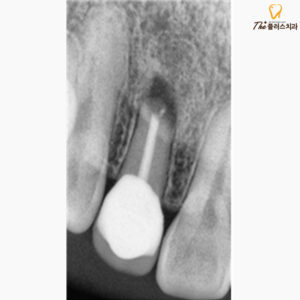

환자분께서도 치근단 절제술 후

증상이 점점 나아졌고,

치아의 흔들림도 적어져

다행이라는 말씀 전해주셨습니다.

정기적으로 검진도 잘 와주신 덕분에

치아 주변의 뼈도 단단하게

다시 차오르는 좋은 양상을 보였습니다.

사진을 보시면 검은색의

투과상으로 보였던 염증 조직들이

깔끔하게 염증 조직들이 제거되며,

그 부위에 잇몸뼈로

차있는 모습을 보실 수 있는데요.

성공적인 치근단 절제술을 진행한 후엔,

시간이 지남에 따라 점차적으로

잇몸뼈가 다시 채워짐을 기대할 수 있습니다.